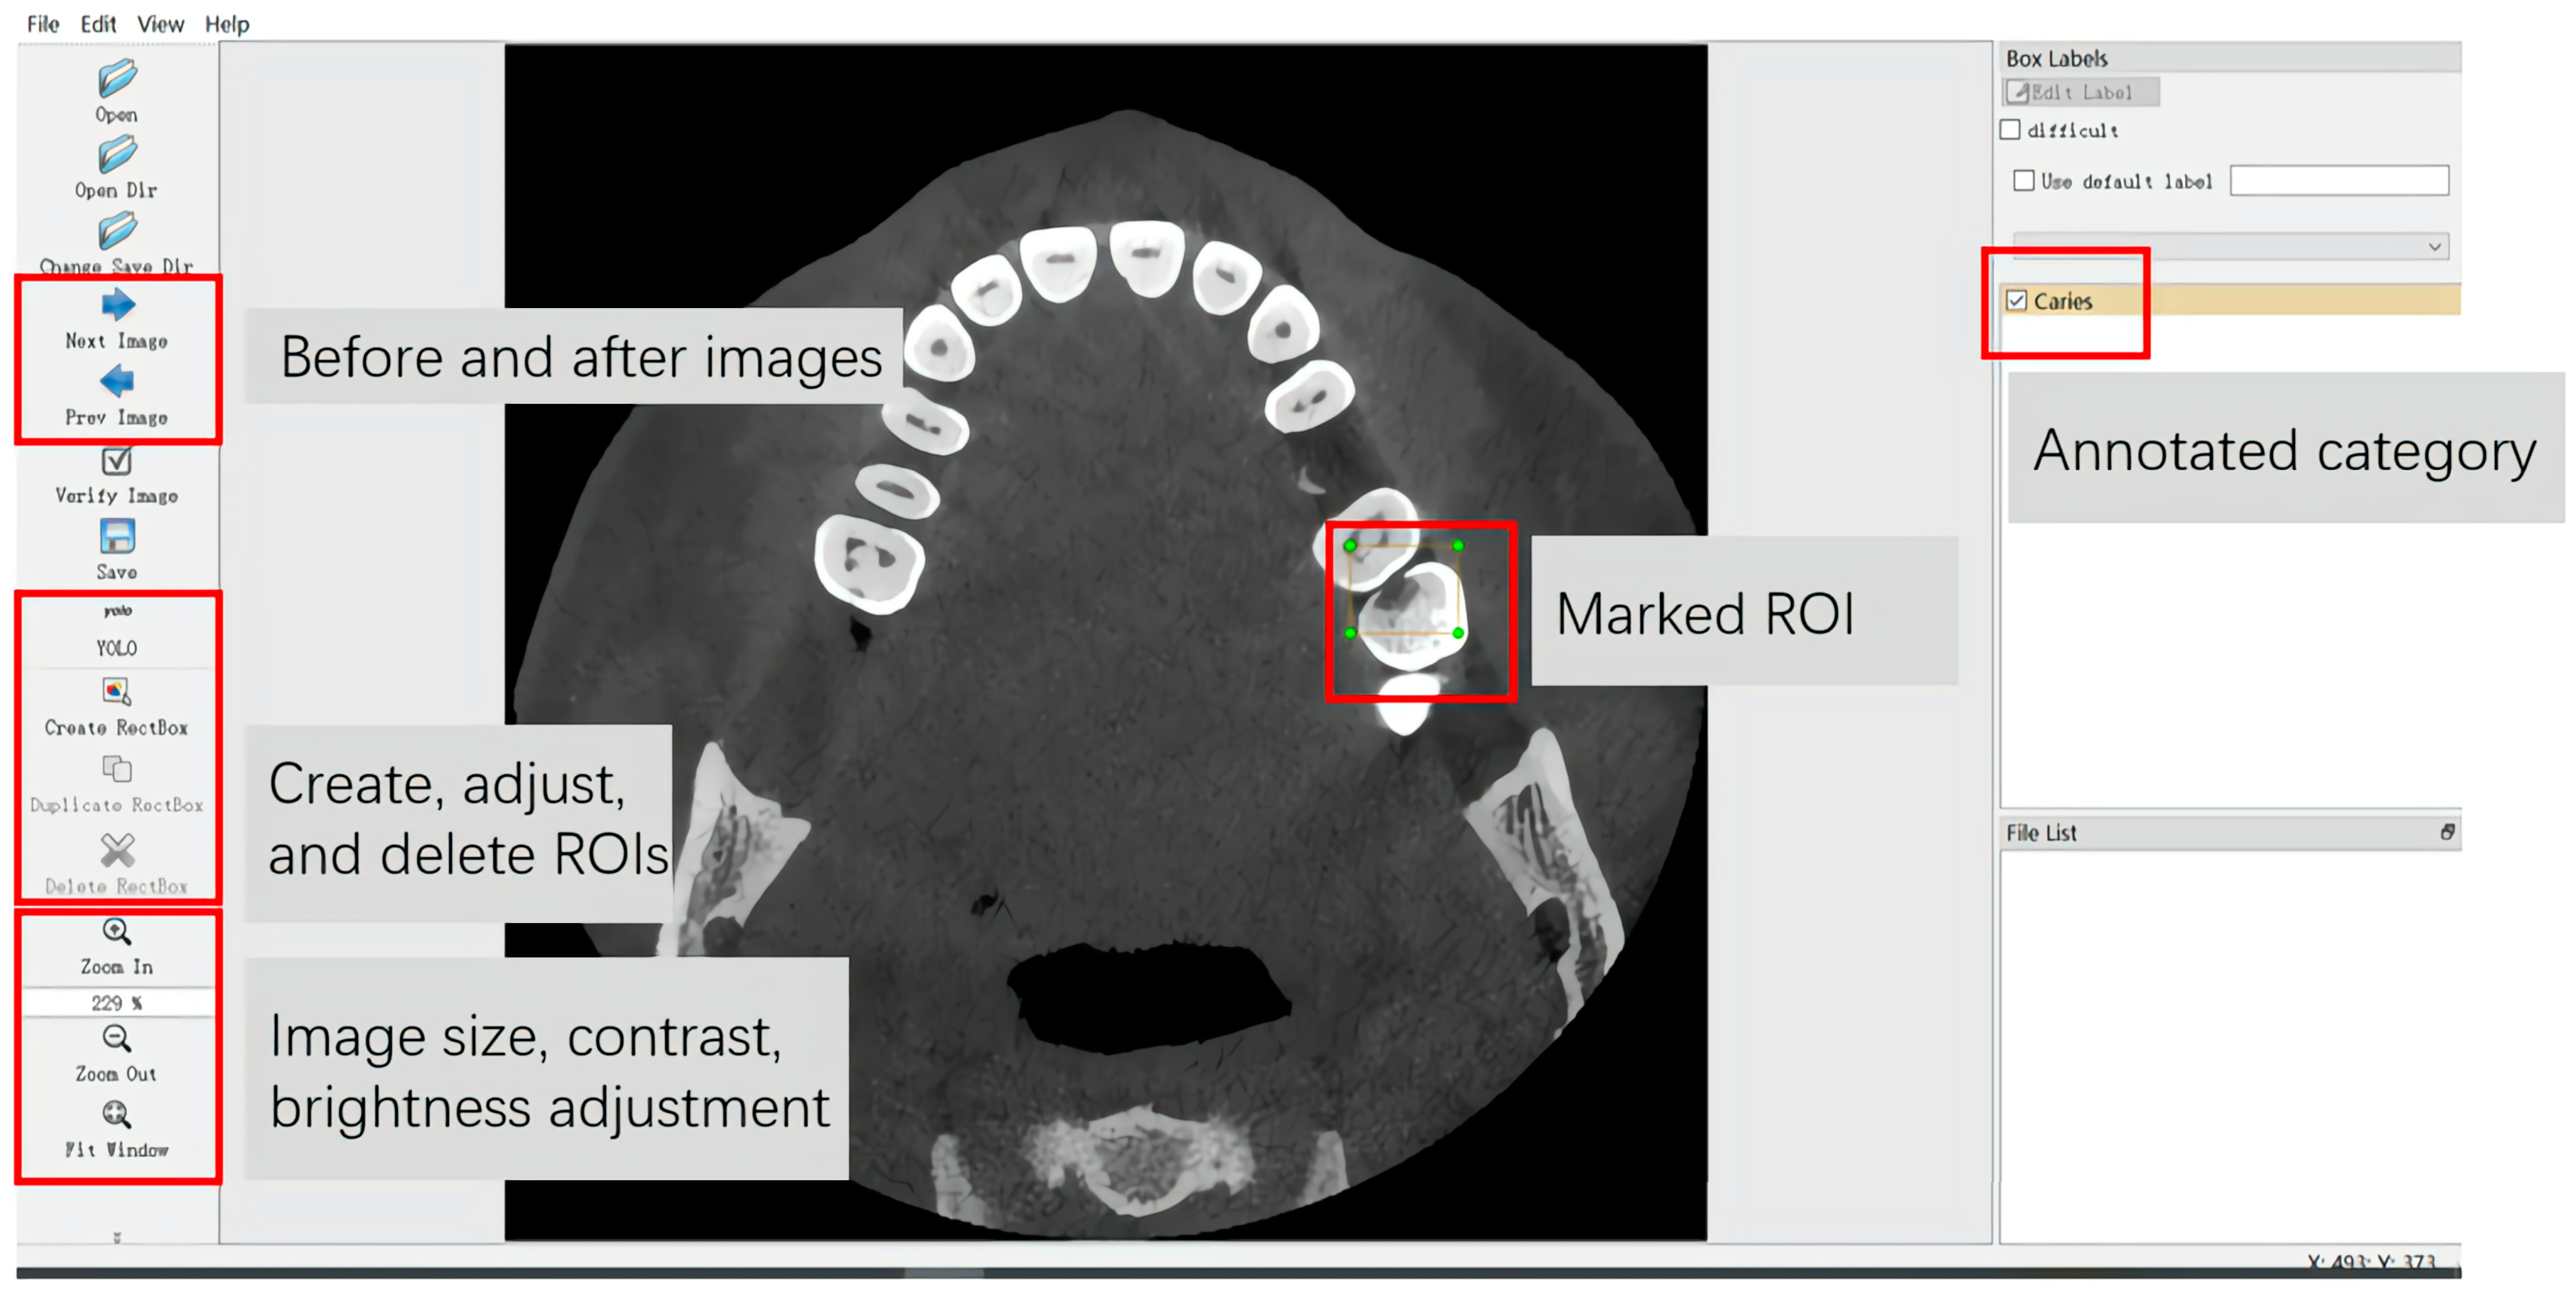

The CBCT images in Dataset 1 and FTG were transformed into the NIFIT format utilising ITK-SNAP software V. 3.8 for preservation. Subsequently, the CBCT axial images were converted into PNG format files, each with a resolution of 512 × 512 pixels and an 8-bit depth, utilising DICOM Converter software (V.1.12.0 DICOM Apps). All slices containing caries were selected from the CBCT axial images in Dataset 1 and the FTG, and each selected CBCT axial image was assigned an independent number, resulting in 2357 images. The same dental radiologist employed the LabelImg software (V.1.8.6 Tzutalin, 2015. LabelImg. Git code.) to annotate all CBCT axial slices featuring caries-affected regions (Figure 3), with the category labelled as “Caries”.

Figure 3. Annotation interface of YOLOv5n. The red boxs and gray squares indicate the meaning of keys.